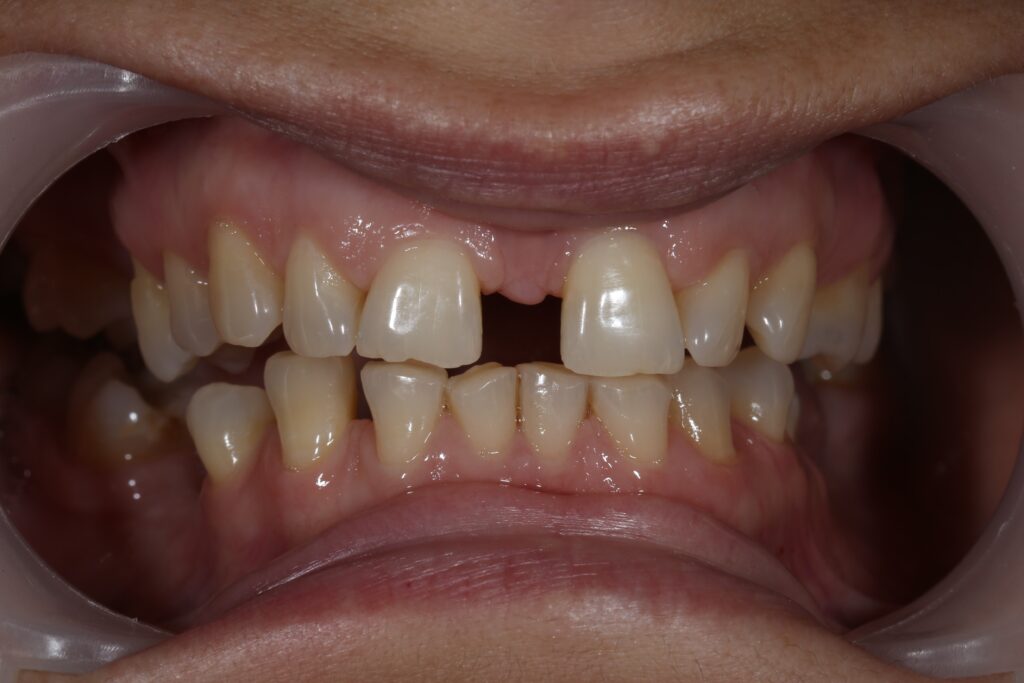

Ситуация до лечения

Пациентка 39 лет была направлена стоматологом-ортопедом для ортодонтической подготовки перед протезированием.

Из-за множественных давних удалений жевательных зубов, произошла деформация зубных рядов, зубы разъехались в область удаленных, что затрудняло протезирование в момент обращения к ортопеду.

Так же можно отметить сильное снижение высоты прикуса (верхние зубы на 100% перекрывали нижние, что вызывало хроническую травму десны), а также повышенную стираемость твердых тканей зубов,

что является следствием повышенной нагрузки, которую много лет испытывали передние зубы, в связи с отсутствием жевательных зубов.

пациент до брекетов